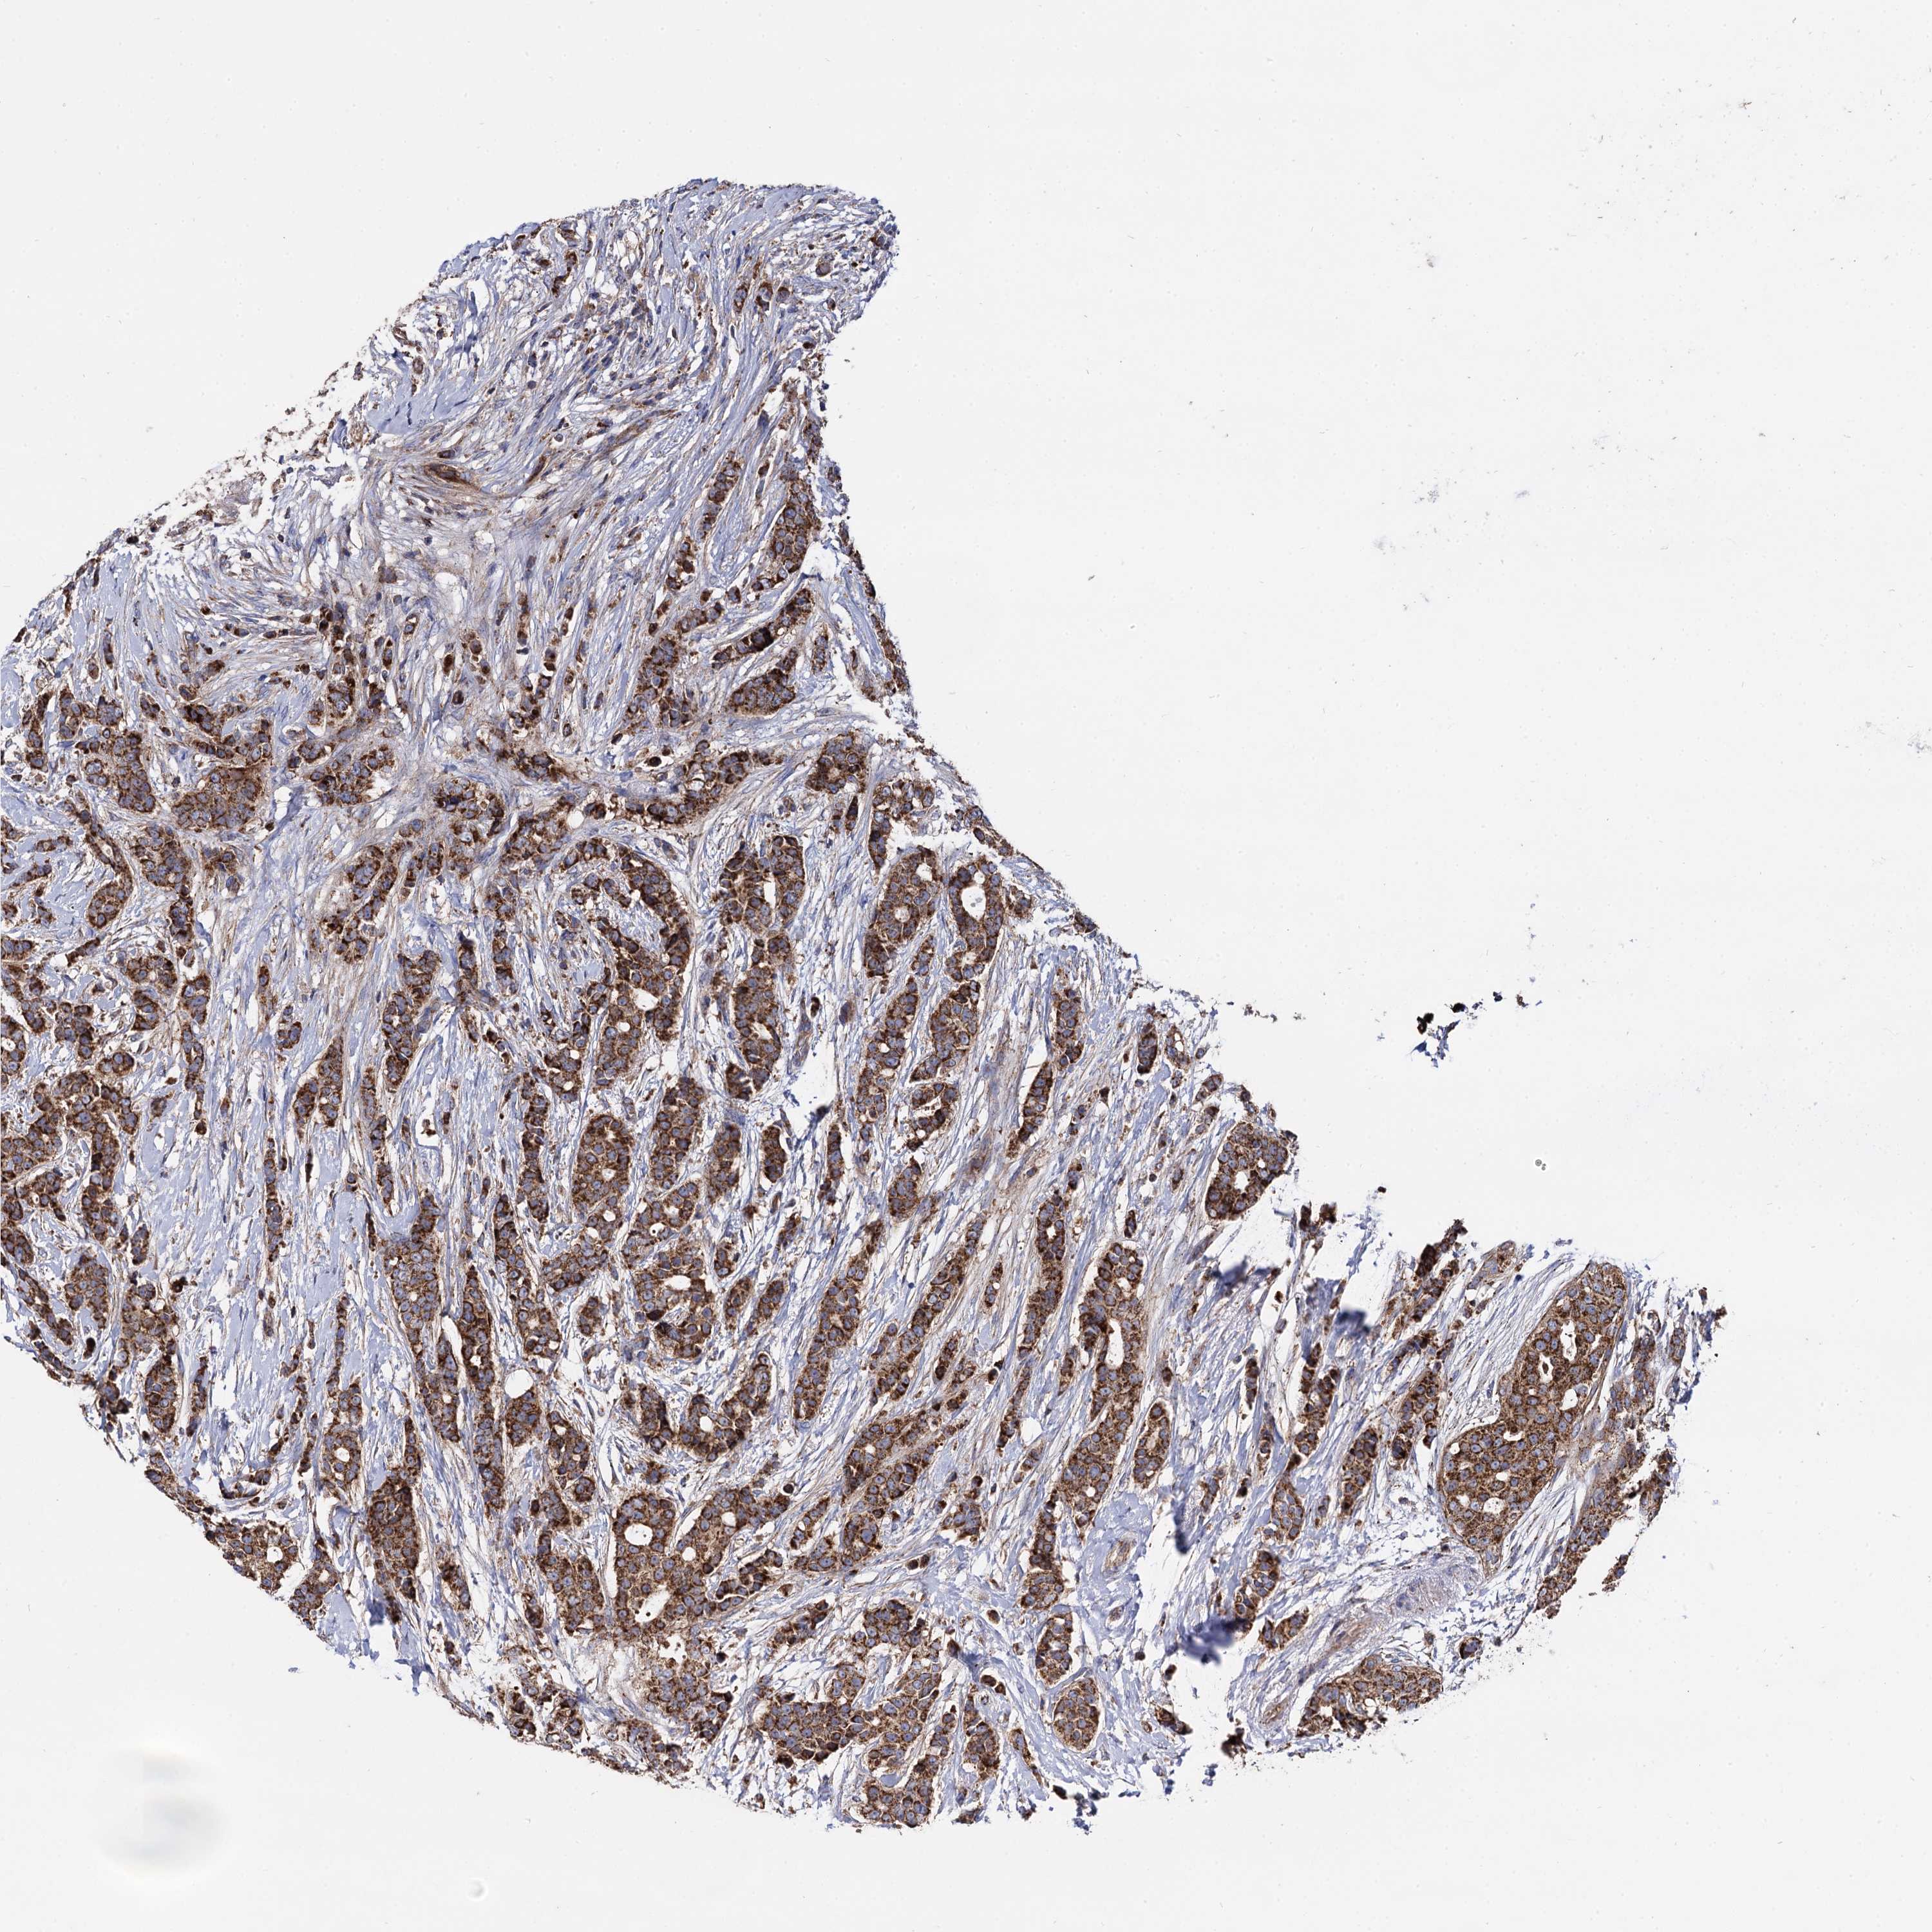

CANCER BREAST CANCER Show tissue menu

BRCA TCGA BRCA VALIDATION PROTEIN EXPRESSION

ANTIBODIES

AND

VALIDATION